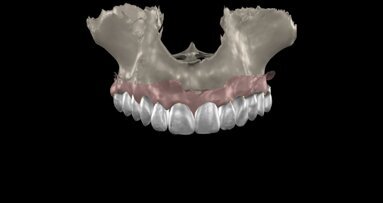

The patient was seen post-surgically after two weeks for suture removal; no untoward post-operative symptoms were noted. The patient was put on a 2 week, 1 month, 3 month and 6-month recall, ensuring the proper management of implant site. An interim fixed resin-bonded retainer (Maryland Bridge) was utilised during the healing phase. After 5 months, prior to second stage surgery, a post-graft CBCT (Figs. 7a–d) was performed and a horizontal bone gain of 5.3 mm was noted. A comparison of pre- and post-operative CBCT images revealed the extent of bone volume achieved (Figs. 8a & b). The patient was recalled for second stage surgery, where the titanium membrane was removed and the healing collar placed (Figs. 9a & b).

After 3 weeks of additional healing, fixture level impressions were accomplished for the laboratory phase. (Impregum 3M ESPE). The final single tooth implant-supported prosthesis can be seen in Figs. 10a & b. The post-insertion radiographic image at 14 months revealed excellent bone adaptation surrounding the implant, with sufficient interproximal height of bone (Fig. 11).